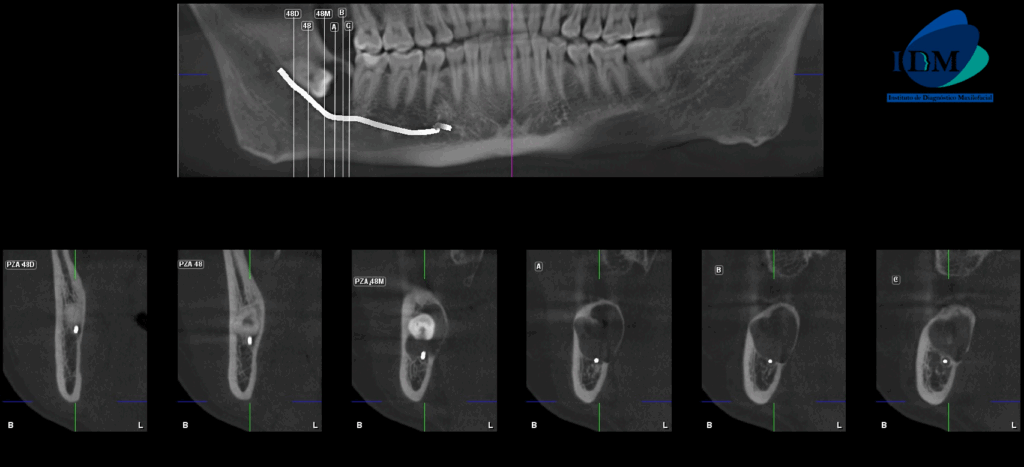

En la radiografía panorámica (Figura 1), se aprecia mineralización parcial de los procesos estilohioideos, neumatización alveolar de senos maxilares, imagen radiolúcida pericoronaria en pieza 48, de limites definidos, bordes corticalizados, que se extiende hasta distal de pieza 47.

A la evaluación de la tomografía volumétrica (CBCT) en los cortes axiales (Figura 2) y transaxiales (Figura 3), se aprecia imagen hipodensa peri coronaria, de limites definidos, bordes corticalizados, que se extiende en sentido cefálico caudal desde cima del reborde alveolar hasta cortical inferior del conducto dentario inferior, en sentido mesio distal desde distal de pieza 47 hasta tercio medio coronal de pieza 48, ocasionando el borramiento parcial de lamina dura de pieza 47 y cortical superior del conducto dentario inferior, adelgazamiento de tabla ósea vestibular y lingual.

CORTES TRANSAXIALES